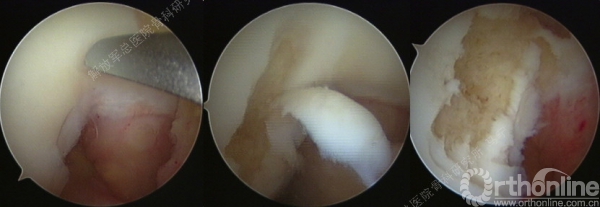

软骨损伤区的清创。

![R53XL~SAG$@@~L%N]I7SRPN.png](/sites/default/files/ueditor/styles/600xno_wartermark/20160422/1461290202_100647.png)

软骨缺损范围的测量。

复位后屈伸膝关节,观察补片情况。